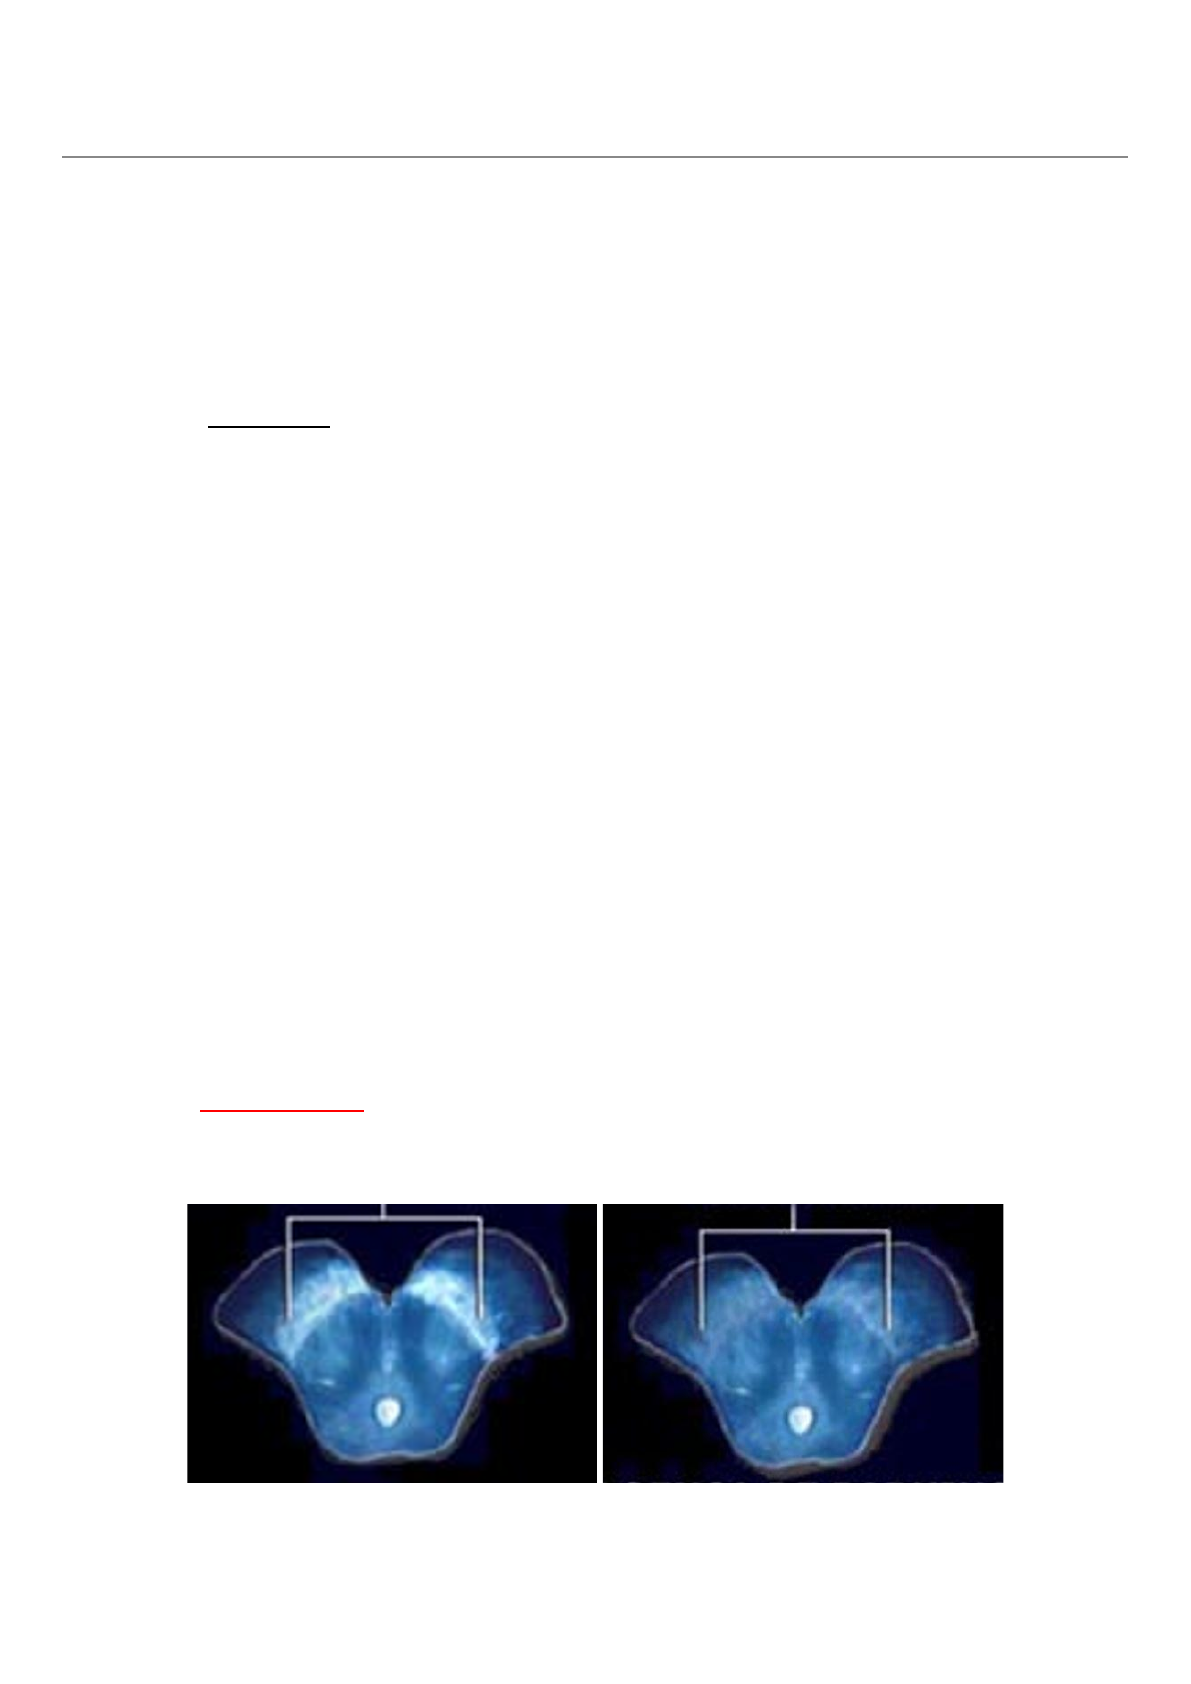

Observe a perda da intensidade do sinal na região da substância negra na imagem à direita.

Sinal da cauda da andorinha

Trata-se de um sinal normal e esperado no paciente saudável; na Doença de Parkinson, esse sinal se torna

degenerado, borrado, ou apagado, como na imagem abaixo: